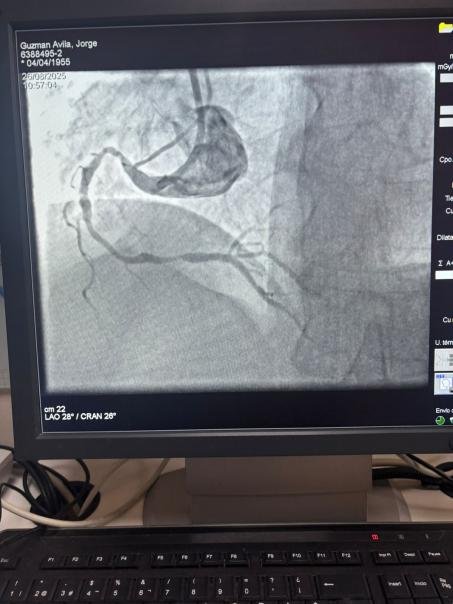

We are proud to share a remarkable case from Hospital Sótero del Río, Chile, where Dr. Martín Valdebenito successfully treated a heavily calcified lesion in the right coronary artery (first curve) using our Vesscrack Coronary IVL Balloon Dilatation Catheter System.

The comparison between the pre-procedure and post-procedure angiographic images clearly demonstrates the significant clinical impact of our IVL technology.